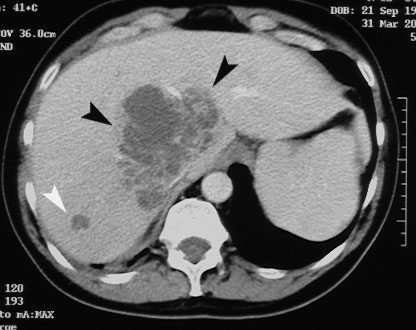

Even though Gemella morbillorum infection (GMI) is rare in humans, it may, nevertheless, cause endocarditis, meningitis, brain abscess, pleural empyema, nephritis, mediastinitis, and – occasionally – liver abscess. We are describing the case of a 64-year-old Caucasian male admitted with fever and abdominal pain. Laboratory parameters revealed inflammation signs, and instrumental examinations showed the presence of diverticula in the ascending colon. Abdominal ultrasound (US) and computer tomography (CT) showed two focal lesions in the right liver lobe. One had the characteristics of a simple cyst; the second was hypoechoic with a low density area, possibly containing necrotic material. US-guided needle biopsy was found negative for neoplastic cells, showing purulent infiltrate. Pus culture was found positive for GMI. Systemic antibiotic therapy, coupled with repeated US-guided needle aspiration, induced the resolution of the hepatic abscess. Few cases have been reported of hepatic abscess caused by GMI in immunocompetent non-cirrhotic subjects.Authors